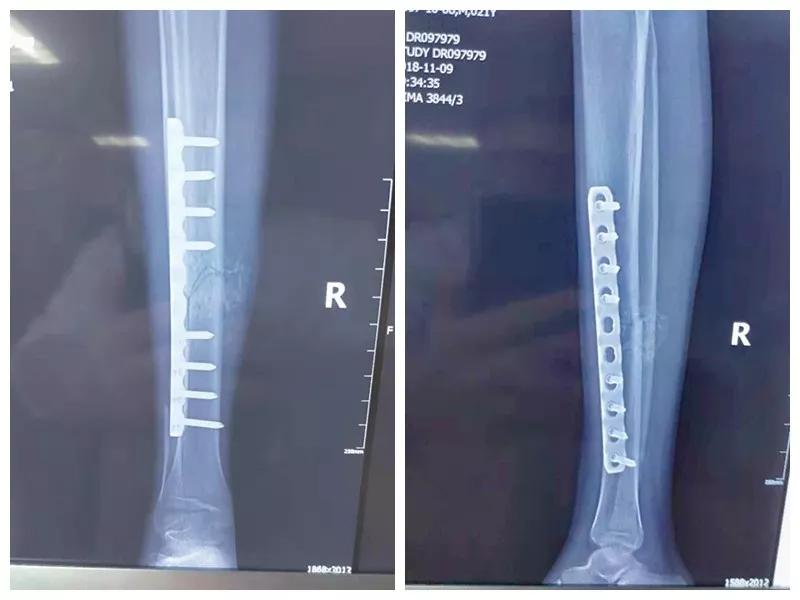

骨二科张延平主任接诊后经仔细询问病史,详细阅读近期X线、CT等病历资料,认为患者骨折移位明显,目前骨折无任何愈合迹象,若保守治疗,骨折将无法愈合,后期不能下地活动,严重影响患者生活质量。同时患者合并慢性再障,血常规结果各项指标均极低,围术期发生麻醉意外、大出血、感染等风险极高;而我院作为西安市级最大的三甲综合医院,综合实力深厚,既往相关疾病治疗经验丰富,多次通过多学科诊治为合并复杂内科疾病患者保驾护航,为患者创造手术时机,提高患者生活质量,遂将患者收住院。住院后,立即成立了由张延平主任、杨寅副主任、山卉护士长、梁晨主治医师、刘邦定主治医师、李鑫护师组成的手术治疗小组。经初步检查,患者血常规结果较当地检验结果更差,三系细胞均极低,其中血小板仅为1(正常值为100-300),血红蛋白55g/L。遂立即请血研所李罡灿主任医师会诊,给予升高白细胞、纠正贫血、升高血小板等治疗,经积极治疗患者血常规各项指标均较入院时改善。张延平主任再次组织由血研所李罡灿主任医师、麻醉科崔晓岗主任、感染科付建军主任、药剂科韩小年副主任药师等参加的术前讨论。讨论后一致认为患者目前各项指标虽然较入院时改善,但因其慢性再障病史长,骨髓造血及储备能力极差,围术期发生大出血、伤口感染甚至全身感染等风险仍极高,术中及术后需准备大量血小板防止大出血,同时需高度警惕手术切口、取骨区术后发生感染。为尽快为患者施行手术,治疗小组积极联系输血科为患者备血,并为患者制定了围术期抗感染方案;在我院输血科存血量严重不足的状态时,输血科张养民主任亲自联系市中心血站为患者准备手术中及术后所需的血小板制品。手术小组为患者制定了周密的手术方案及风险预案,10月31日,在麻醉科王永宏副主任医师、手术室高洁、赵耀护师的配合下,为患者施行了右胫骨粉碎性骨折切开复位、髂骨取骨植骨内固定术,手术历时70分钟,安全返回病房。术后患者渗血多,1周内连续每日平均渗血超过100ml,并出现发烧,最高39℃,复查血常规三系细胞较术前再次明显降低。李罡灿主任医师、付建军主任、韩小年副主任药师多次来科会诊,及时调整患者的治疗方案,输血科再次为患者的救治提供了强有力的支援和保障。在山卉护士长带领的护理团队精心护理下,患者未发生压疮等卧床并发症。目前该患者术后恢复良好,已出院进行下一步康复治疗。